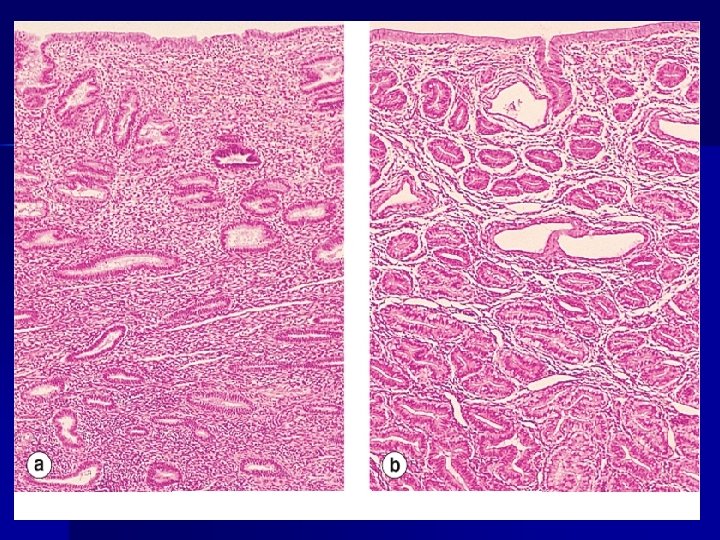

Myocardial hypertrophy

HIPERPLASIA

HIPERPLASIA n n n Constituye el incremento del número de células de un órgano o tejido. Habitualmente se acompaña de hipertrofia. Se produce únicamente en las células capaces de sintetizar ADN (células epiteliales, hematopoyéticas y de l tejido conjuntivo)

Tipos de hiperplasia HIPERPLASIA FISIOLÓGICA n Estimulación hormonal n Compensadora MECANISMOS: Acción combinada de factores de crecimiento α, citocinas (TNF α e IL 6). Las células deben ser estimuladas por acción de mitógenos. La norepinefrina y la insulina potencian los efectos de los factores de crecimiento y de las citocinas. La interrupción del crecimento se debe a la acción de factores inhibidores del crecimiento β.